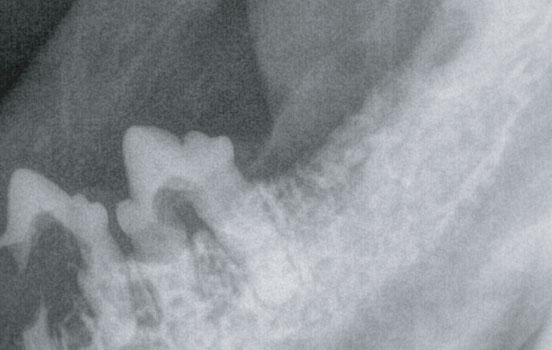

육안적으로 확인되는 경우도 있으나, 정확한 평가를 위해서는 치과 방사선을 촬영해 봐야합니다.

병변이 관찰될 경우, 영향을 받은 치아 뿐만 아니라 전체 치아를 발치해야 하기 때문에

정확한 진단과 치료가 필요합니다.